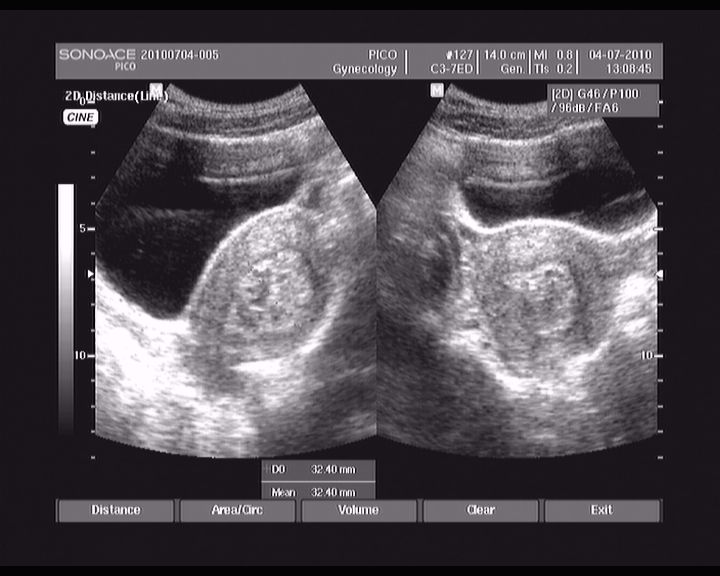

abrasio 01.07.2010

113.jpg